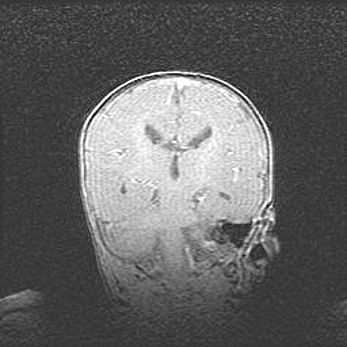

Аномалия Денди-Уокера. Признаки гипоплазии мозолистого тела.

Возраст: 5 месяцев 3 дня

Вес: 5550 г

Пол: мужской

Окружность головы: 39 см

Срок гестации: 40 недель

Аномалия Денди-Уокера – это порок развития головного мозга, для которого характерна триада симптомов: гипотрофия или аплазия червя мозжечка и/или полушарий мозжечка, расширение четвёртого желудочка с формированием ликворной кисты задней черепной ямки, гипертензионная гидроцефалия различной степени.

Гипоплазия мозолистого тела относится к дефектам внутриутробного этапа развития мозговой ткани, возникающим в процессе закладки структур головного мозга, что происходит на начальных этапах развития эмбриона.